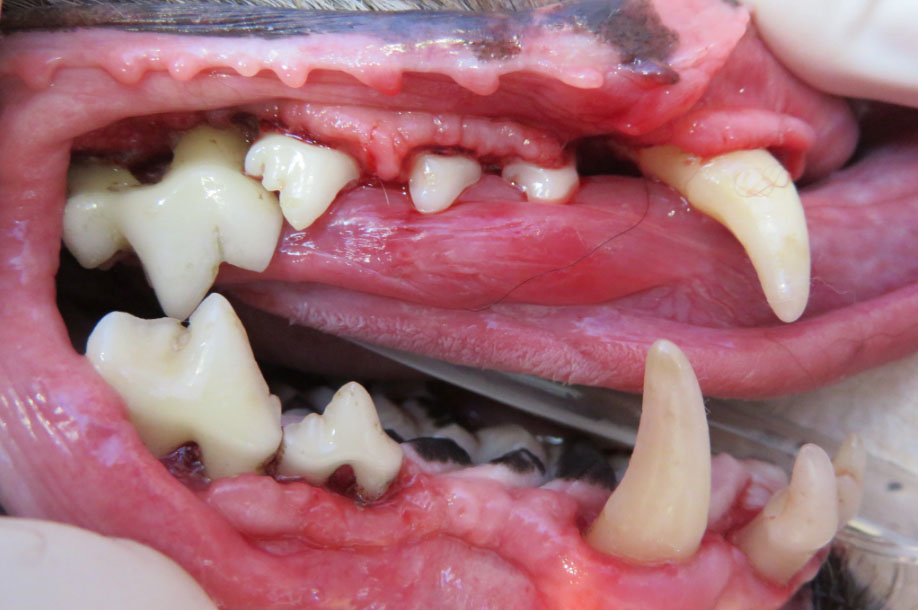

これはうちの愛犬コポーの歯です

まだ子犬なので、さすがにきれいです

このように

上のワンちゃんの歯石を取ったのが下の写真です

奥歯の歯根分岐部が露出してしまっています